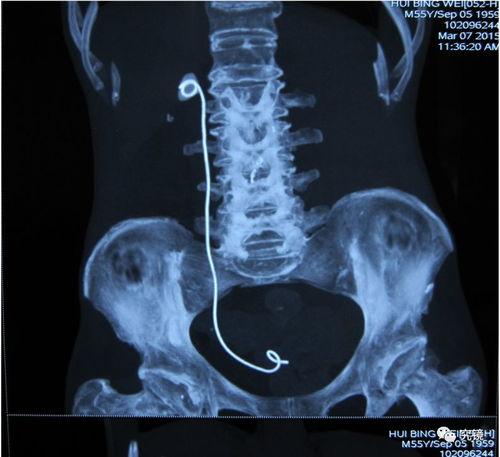

首先,得先弄清楚什么是双J管。双J管是一种医疗器械,主要用于治疗尿路结石。而拔双J管视频,就是记录了医生为患者拔除双J管的过程。听起来是不是有点不可思议?但别急,接下来我会详细解释。

观看拔双J管视频,就像亲临现场一样。你可以看到医生如何操作,患者如何配合,以及手术过程中的种种细节。这种真实感让人既紧张又好奇,仿佛能感受到患者的痛苦和医生的专注。